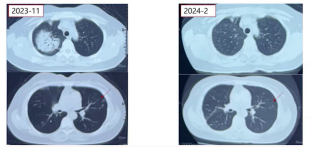

3.胸部CT

1)2023年11月(首次发病):右肺上叶实变影,左肺上叶多发小结节影。

2)2023年12月(激素治疗2个月后):右肺上叶实变影明显吸收,左肺上叶阴影仍存在。

3)2024年6月:左肺上叶小结节影、斑片影及左下叶小结节较前加重。

2023年12月,患者予泼尼松抗炎联合异烟肼、左氧氟沙星治疗后症状明显好转;激素治疗2月后复查CT,示右肺病变明显吸收,左肺上叶小结节影大致同前,遂停用左氧氟沙星,继续口服泼尼松、异烟肼及利福平。